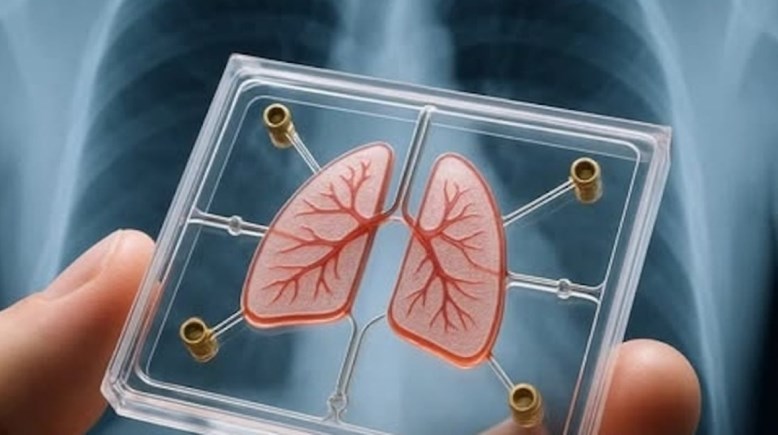

خطوة نحو الطب الشخصي

طريق جديد للعلاج، "رئة مصغرة" لفهم الأمراض التنفسية بدقة